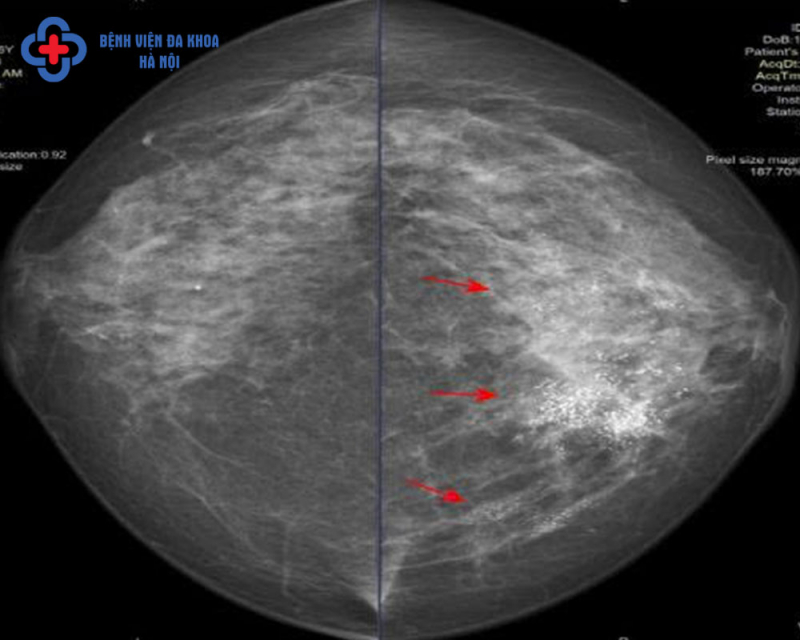

Tại Bệnh viện Đa khoa Hà Nội, chị H. được chụp nhũ ảnh trên máy X-quang 3D (Mammomat Inspiration), kết quả cho thấy nhiều bất thường về cấu trúc, hình thái nghi ngờ ung thư ở cả hai bên vú. Khi chụp cộng hưởng từ tuyến vú, thấy rõ khối u vú đa ổ hai bên nghi ngờ với tính chất ngấm thuốc mạnh, chưa xâm lấn các cấu trúc và cơ quan lân cận. Kết quả sinh thiết lõi khối u cả hai bên vú đều là u ác tính. Ngay sau đó, chị H. được tư vấn điều trị chuyên khoa.

Tương tự, chị H.T.K. (47 tuổi, Hà Nội) cũng được chẩn đoán u lành tính ở vú trái trước đó và theo dõi… Cho đến khi chị K. đến Bệnh viện Đa Khoa Hà Nội chụp nhũ ảnh thì phát hiện phần lớn mô vú có vi vôi mật độ dày đặc dạng đa hình, dạng nhánh, dạng đường mảnh kèm xáo trộn cấu trúc nghi ngờ ung thư. Kết quả sinh thiết là ung thư biểu mô ống tuyến vú.

Cũng theo Ths. BS CKII Đỗ Đức Linh, thực tế khám lâm sàng và siêu âm rất khó phát hiện được các vi vôi hoá - là những đám canxi lắng đọng, rất đa dạng về hình thái, kích thước, số lượng và sự phân bố trong tuyến vú. Trong một số trường hợp, vi vôi hóa là dấu hiệu ung thư ở giai đoạn sớm và nhũ ảnh là phương tiện có ưu thế tuyệt đối so với siêu âm và MRI trong việc phát hiện, đánh giá, phân loại những tổn thương dạng vi vôi để có hướng chẩn đoán, xử trí phù hợp. Ngoài ra nhũ ảnh còn giúp hướng dẫn cho sinh thiết nhằm xác định bản chất tổn thương.